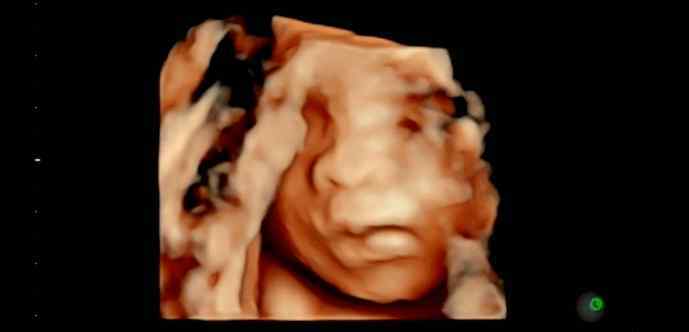

当“他们”第一次见面时,ta丰富的表情清晰可见

她带着3800g的体重来到这个世界。